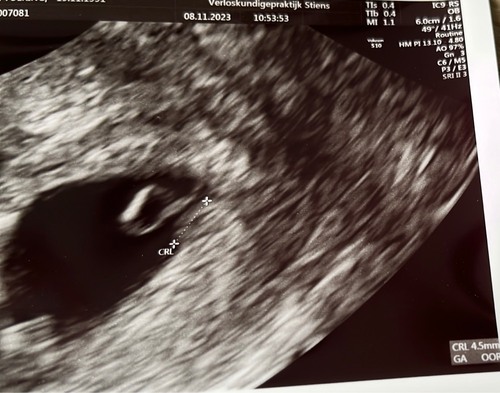

Ik heb zojuist ook de eerste echo gehad. Vruchtje is 5,2mm en ze zeggen dat ...

Heel normaal hoor 馃グ

Hoever ben jij volgens je eigen berekening dan ??